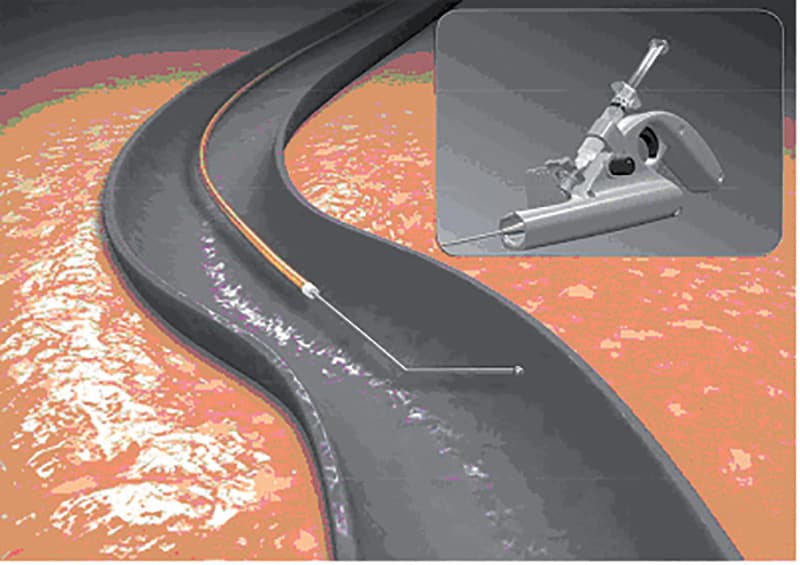

L’OBLITÉRATION VEINEUSE PAR RADIOFRÉQUENCE

Closure est un traitement endovasculaire du tronc de la veine saphène.

Par une mini-incision sous le genou ou par ponction, la sonde Closure est montée dans la veine jusqu’à l’aine.

Son extrémité présente un élément chauffant de 7 cm utilisant la radiofréquence. Le tronc est chauffé par portion de 7 cm de haut en bas sous contrôle échographique peropératoire.

Son extrémité lumineuse permet de le suivre par transparence sous la peau.

Sous l’effet de cette chaleur dont l’induction est rigoureusement contrôlée par ordinateur, la paroi s’épaissit de 98 % et la lumière veineuse se ferme complètement.

Le tronc veineux traité, totalement oblitéré, reste visible sur l’écran de l’échographe pour disparaître complètement au bout de 6 mois.

Les suites pendant les premières semaines sont beaucoup plus légères qu’avec le stripping classique.

La procédure est souvent totalement indolore sur son trajet au niveau de la cuisse.